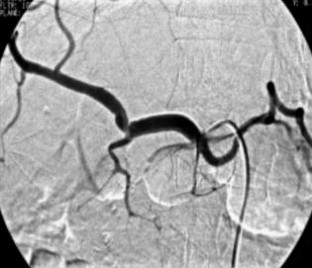

Wir berichten über das diagnostische und therapeutische Vorgehen anhand von 7 Patienten mit Blutungen aus der A. gastroduodenalis (n=5) nach pankreaschirurgischen Interventionen bei Pankreaskopfkarzinom, Rezidiv eines Liposarkoms und chronischer Pankreatitis, der A. hepatica communis (n=1) bei chronischer Pankreatitis und der A. mesenterica superior (n=1) nach akuter Pankreatitis. Anhand von 4 Kasuistiken werden unsere Erfahrungen mit der Implantation von Stentgrafts (Hemobahn®-Prothesen) vermittelt. Den Vorteil der Stentgrafts sehen wir in der sofortigen Blutstillung bei fehlendem Kontakt der Endoprothese zu infiziertem Gewebe und Erhalt der Perfusion des abhängigen Organs. Unsere positiven Erfahrungen mit diesen interventionellen Therapieverfahren erfordern jedoch weitere klinische Untersuchungen, wobei im Mittelpunkt die Indikationen, die technische Erfolgsrate, die stentbedingten Komplikationen und die Langzeitverläufe stehen sollten.

Spontaneous or postoperative hemorrhage into the abdominal cavity due to inflammatory vessel arrosion represents an uncommon but menacing situation. According to the literature, such hemorrhage is associated with a lethality of nearly 2%. Therapeutical options include reoperation and interventional radiological techniques such as endovascular catheter techniques with stent graft implantation or the embolization of vessels. We report on the management of seven cases with hemorrhage either from the gastroduodenal artery (n=5) following pancreatic surgery for pancreatic carcinoma, liposarcoma, and chronic pancreatitis or from the common hepatic artery (n=1) and the superior mesenteric artery (n=1) following chronic pancreatitis. The present article describes our experiences with stent graft implantation (hemobahn prosthesis) in four cases. Based on these experiences, we see the advantages of stent grafts in primary hemostasis without any contact to infected tissue and the preservation of regular perfusion. However, further clinical data are required focussing on indication, technical success rates, stent-related complications, and long-term outcome.